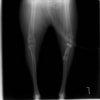

雑種 5歳

左後肢の挙上を主訴に来院されました。触診にて両関節の前方引き出し兆候、両膝蓋骨の内方脱臼を認めました。関節液検査より免疫介在性多発性関節炎は否定的でした。レントゲン検査にてfat pad signを伴う関節炎が認められたことから、前十字靭帯断裂と膝蓋骨内方脱臼(左GradeⅢ 右GradeⅢ〜IV)併発と診断し、手術を行いました。

手術は片足ずつ行い、両膝とも術中の関節鏡検査にて前十字靭帯の完全断裂と半月板損傷を確認しました。TPLO、半月板切除と滑車溝形成を始めとした膝蓋骨脱臼整復術を実施いたしました。膝蓋骨の安定化を測るために外側支帯を強固に縫合し、内側支帯は切除し縫合せずに開放状態にしています。

術後の歩行状態は良好です。

術前正面像

術後左後肢正面像

術前のTPAは左後肢33.1°右後肢26.8°でしたがTPLO実施により左後肢5.5°右後肢12°に矯正されました。